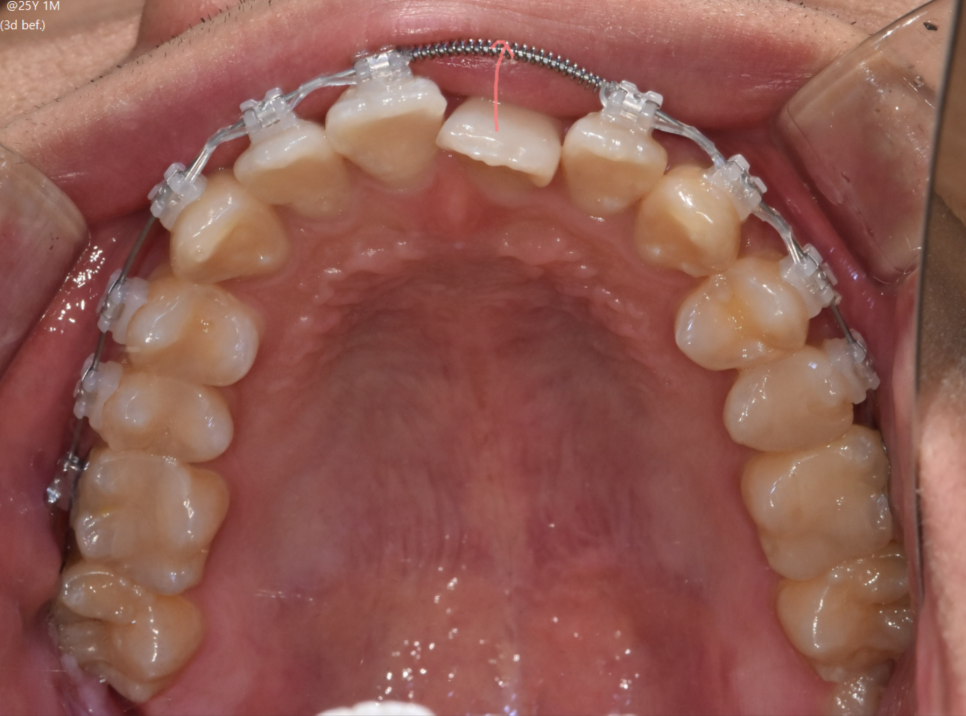

250721

다행히 교합은 정상이었기 때문에

이럴 경우는 앞니 배열을 개선하면 치료가 종결됩니다.

기간도 1년 정도

상대적으로 짧게 소요됩니다.

아래 앞니는 뒤로 보내고

안쪽으로 들어간 윗니는 나오면서

전체 배열 정리가 되겠네요.